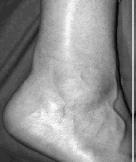

Bij het onderzoek klaagt de patiënt over een langzaam ontstane pijn in de Achillespees, eerst alleen bij belasting, later ook in rust afhankelijk van het klachtenstadium. Kenmerkend zijn de ochtendstijfheid en de startproblemen. Vrijwel altijd zien we een zwelling 1,5- 7 cm boven de hiel

Het heeft geen zin om een röntgenfoto te maken, vaak is de aandoening duidelijk zichtbaar of palpeerbaar. Als er toch nader onderzoek moet worden gedaan dan is met name de echografie geschikt. We kunnen dan tevens bijkomende afwijkingen als Haglundse exostose of een bursitis in beeld brengen. Ook het uitsluiten van een partiële Achillespeesruptuur is van belang.( vaak aan de mediale zijde)